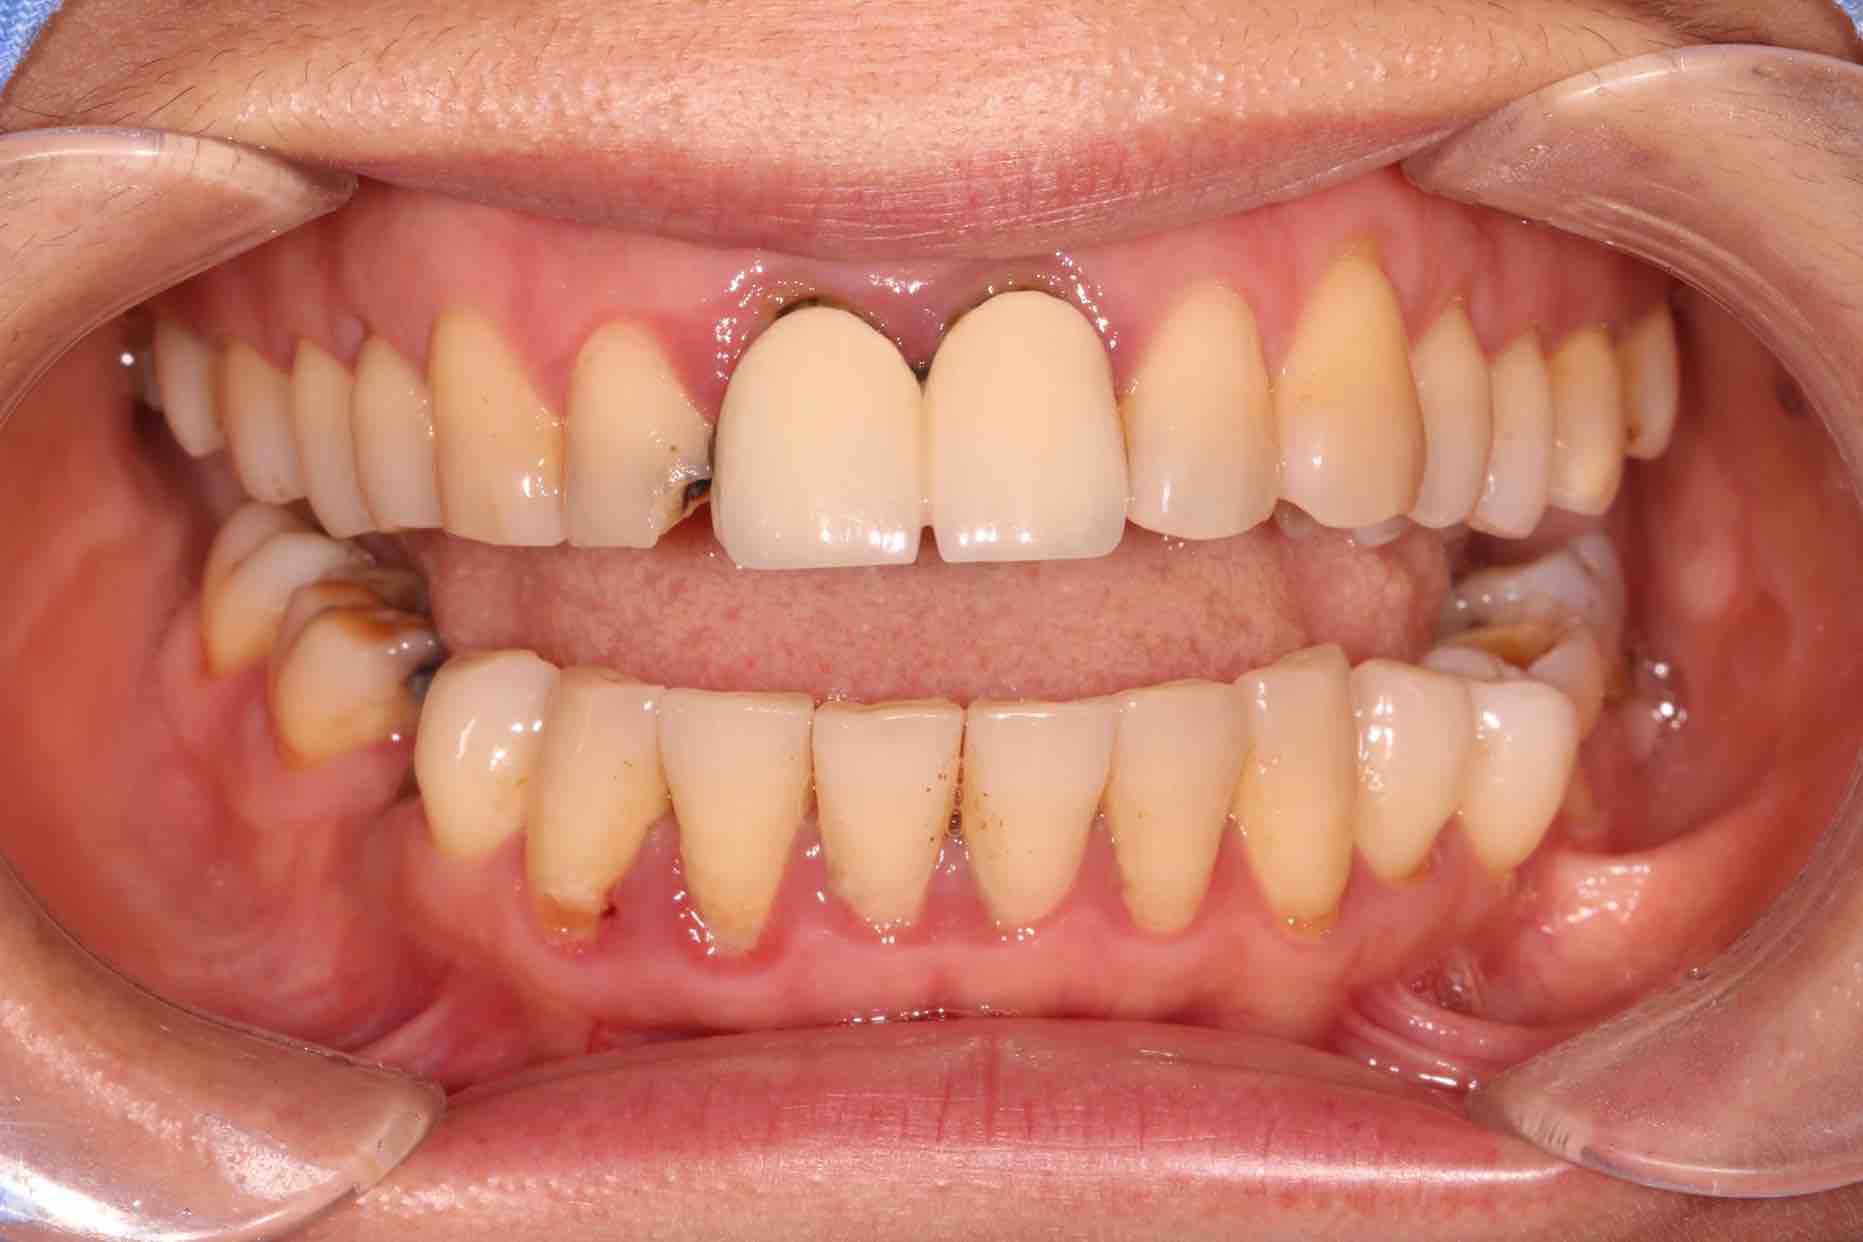

患者中年女性,11、21外院制作烤瓷冠,冠边缘不密合,牙龈退缩发黑,龈缘红肿,颜色不美观且X线检查21根管治疗不完善,由于牙冠不密合,11严重龋坏已有牙髓炎症状,我们对11进行了根管治疗,21进行了根管再治疗,最后CEREC扫描修复。